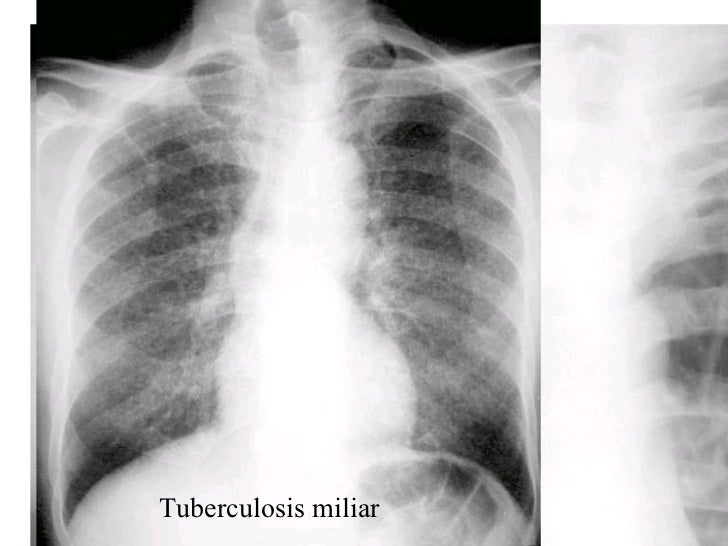

SIGNOS Y PATRONES CLASICOS DE PATOLOGIA PULMONAR EN TC